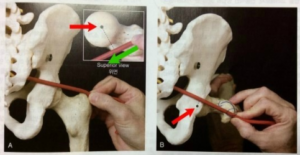

(7) 폐쇄근

폐쇄근은 골반의 폐쇄공에서 시작하여 대퇴골로 연결된 근육입니다.

외폐쇄근과 내폐쇄근이 있으며 수축 시 고관절의 외회전을 유발합니다. (왼쪽 : 외폐쇄근 / 오른쪽 : 내폐쇄근)